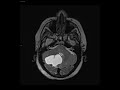

Hemangioblastoma

These images demonstrate a cystic mass in the right cerebellar hemisphere with an enhancing nodule along its posterior aspect. There is mild mass effect on the posterior right aspect of the 4th ventricle which remains patent. There is slight downward displacement of the cerebellar tonsils. In an adult, findings are classic for hemangioblastoma. These can be sporadic or associated with Von Hippel Lindau. This patient was an elderly female, but this these are typically found in young adults with a male predilection. Polycythemia may develop.